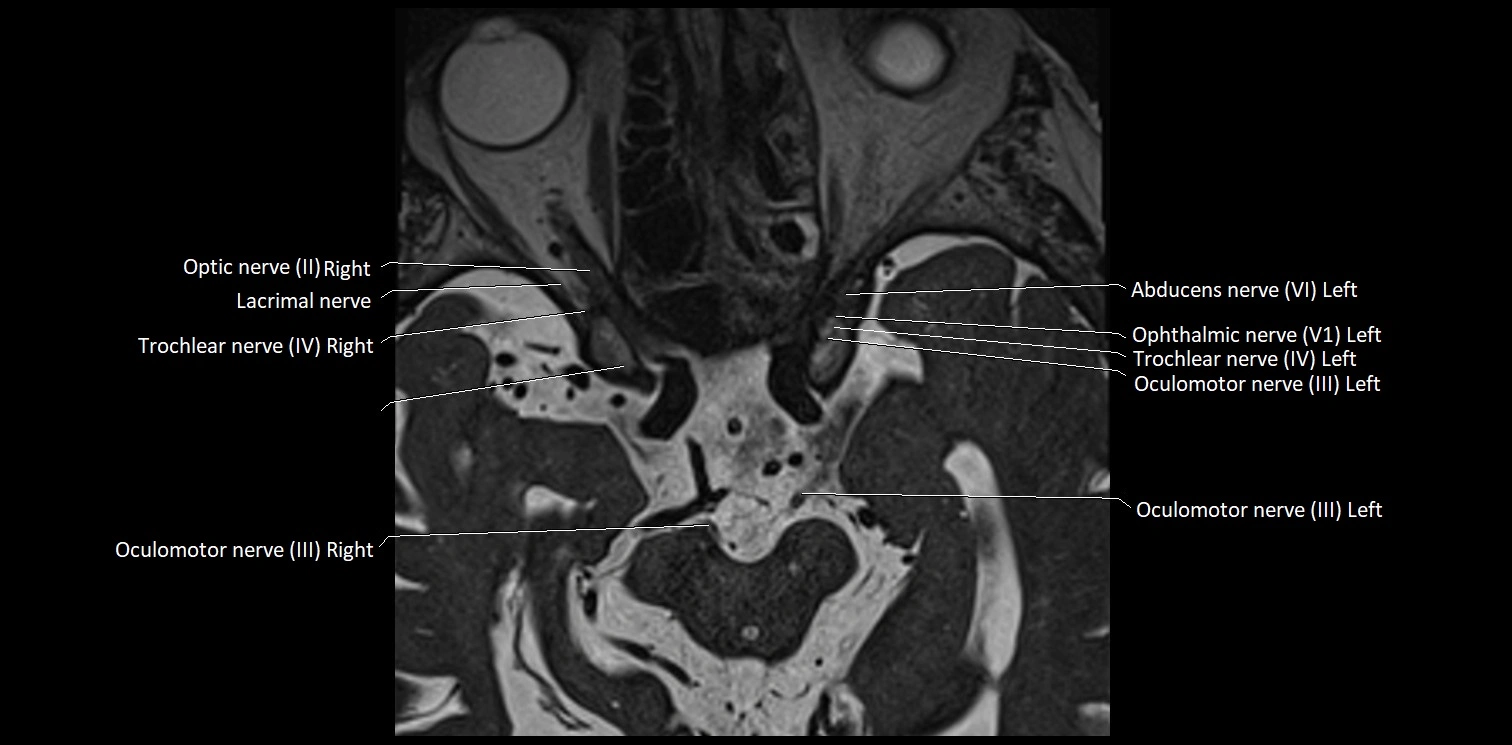

MRI Appearance

• The abducens nerve is a small, thin, linear structure

• Best visualized on high-resolution T2-weighted 3D MRI sequences (e.g., FIESTA or CISS)

• Seen as a hypointense (dark) line running from the brainstem at the pontomedullary junction, traversing the prepontine cistern, and entering Dorello’s canal under the petrosphenoidal ligament, then into the cavernous sinus, and finally the orbit

• May be challenging to visualize in standard MRI due to its small size

• Pathology may be inferred by absence, displacement, or enhancement of the nerve

MRI images

image